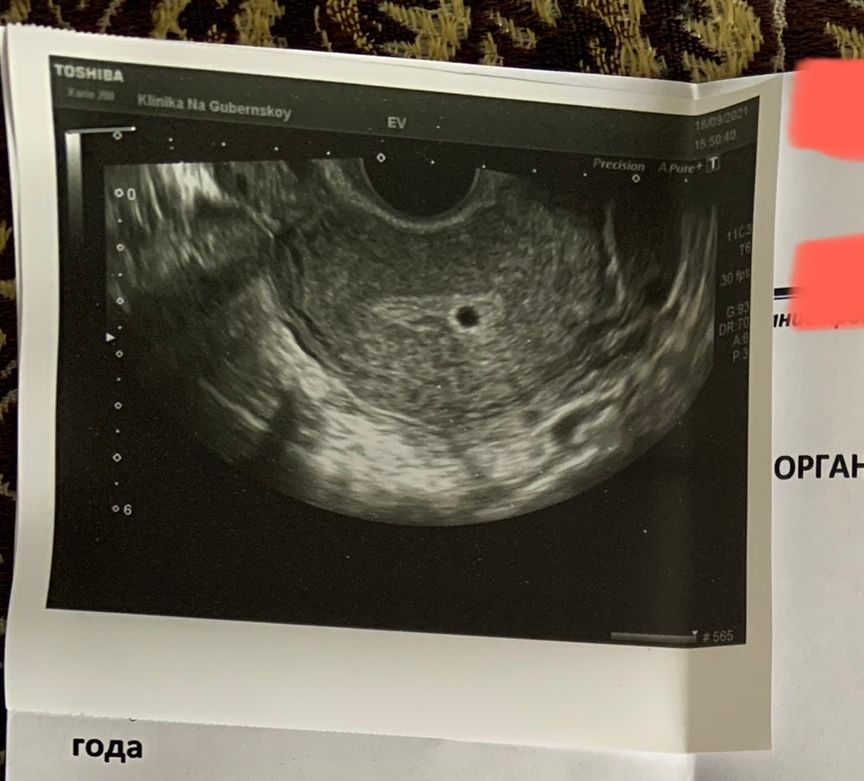

Изображение

На 31 дпп пошла на УЗИ в платный центр. По УЗИ пя 0,5 мм.Не эмбриона не жм не сб естественно нет .Узист посоветовала прийти на УЗИ через 10 дней. Дала маленькую надежду. Жду))